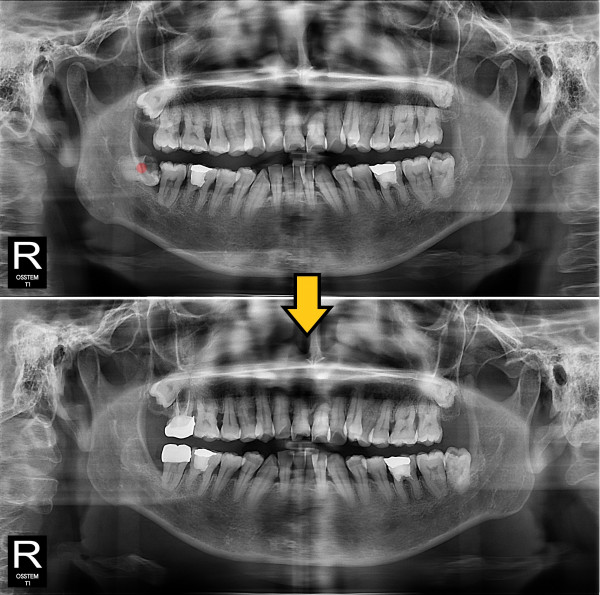

사랑니발치 30대/여성

ae27575af29d49719312fde5a1f0cca6_1764402230_7515.jpg